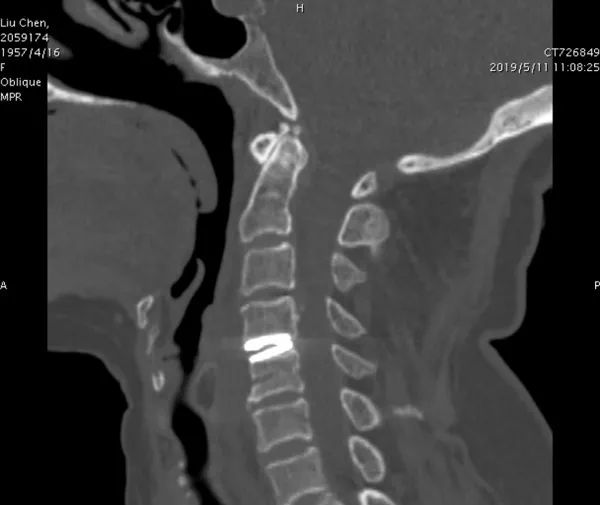

今年52岁的患者刘女士来自陕西省洛南县,5个月前出现了左上肢胀痛、麻木和无力症状,且伴有走路不稳。经过详细检查,医生发现刘女士颈4/5巨大椎间盘突出。采访中,院长郝定均说:“患者年龄不大,颈椎稳定性好,颈椎退变增生不严重,颈椎间盘突出节段少。如果按常规给她实施颈椎间盘减压融合术,固定节段活动度丧失,术后可能出现临近节段退变而需要再次手术治疗,后续治疗曲折,得不偿失。”由此,3D打印技术被提上方案。

红会医院脊柱病医院退变与肿瘤病区主任单乐群表示,3D打印人工颈椎间盘假体是基于患者的影像资料,先重建患者自身的颈椎3D图像,再根据图像资料设计并量身定制出最符合患者的个性化假体,3D打印出来假体后应用于患者手术。

3D打印人工颈椎间盘置换,可为每一位患者量身制定个体化的人工颈椎间盘,从而有效降低术后相关手术并发症的发生。